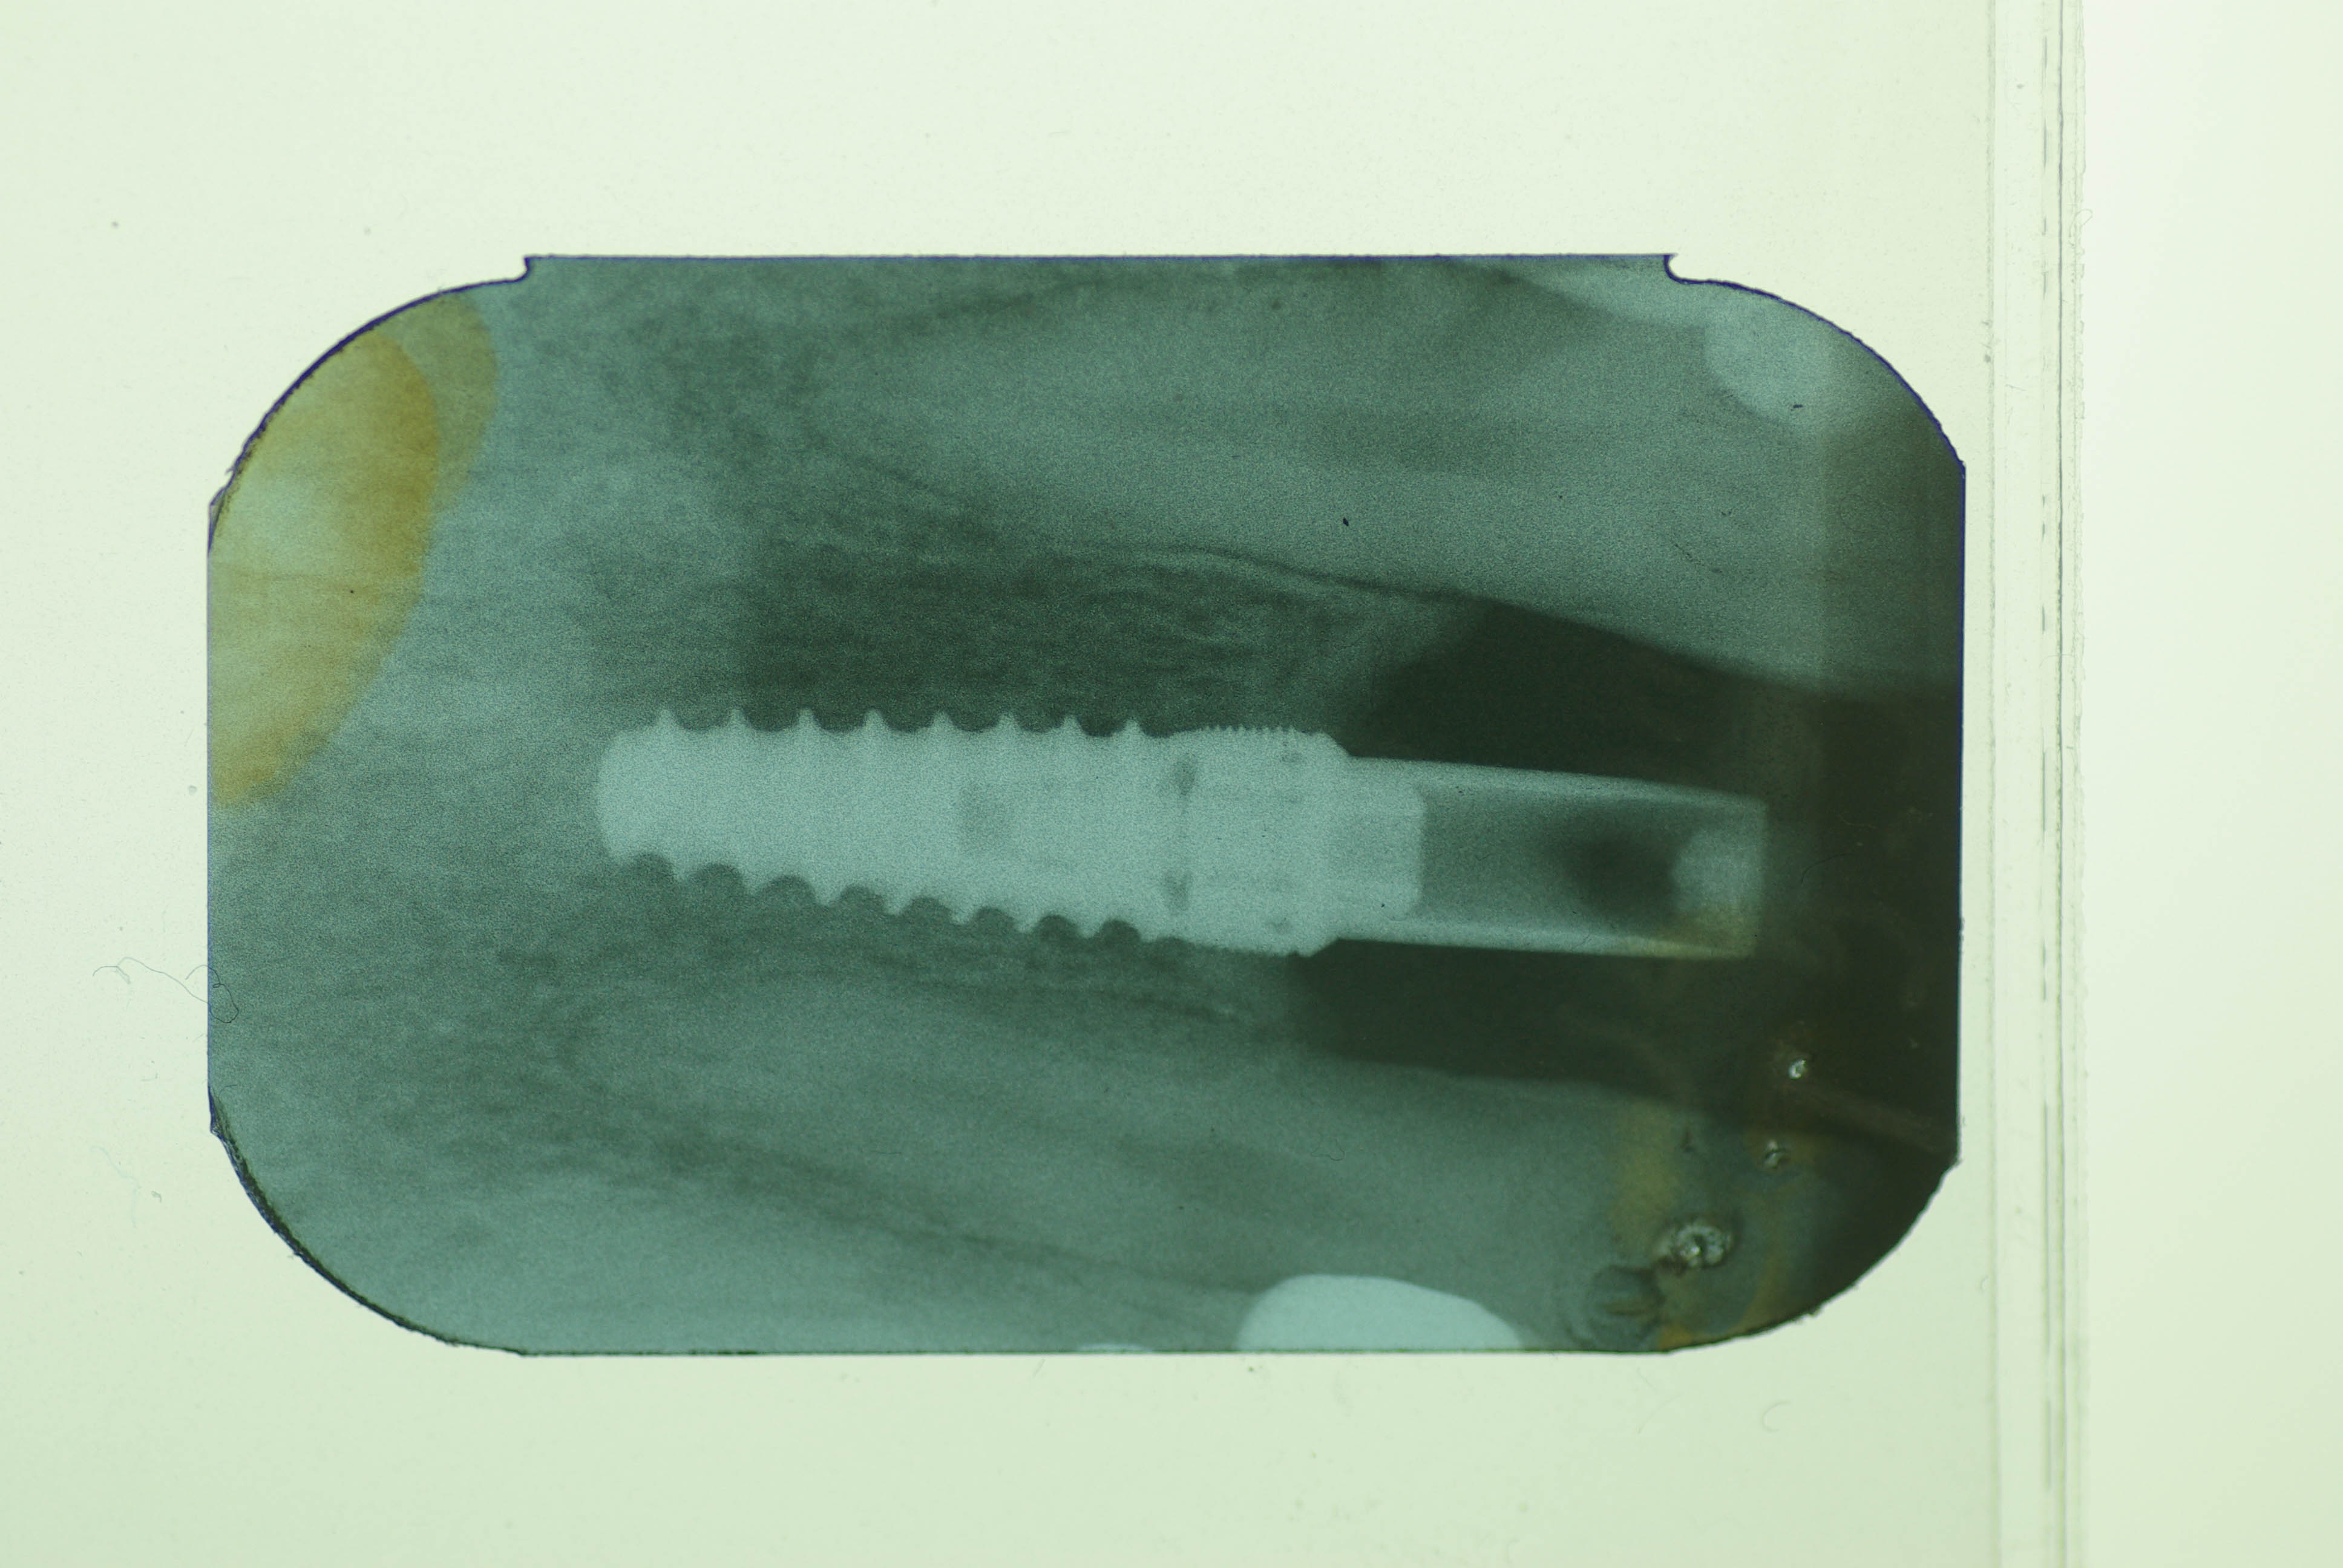

bonjour nous pensions à du MIS seven mais le pilier ne correspond pas le tournevis zimmer est ok pour la tete de vis prothétique néanmoins.

camlog ?

Intra lock

http://osseosource.com/dental-implants/product_info.php?products_id=384